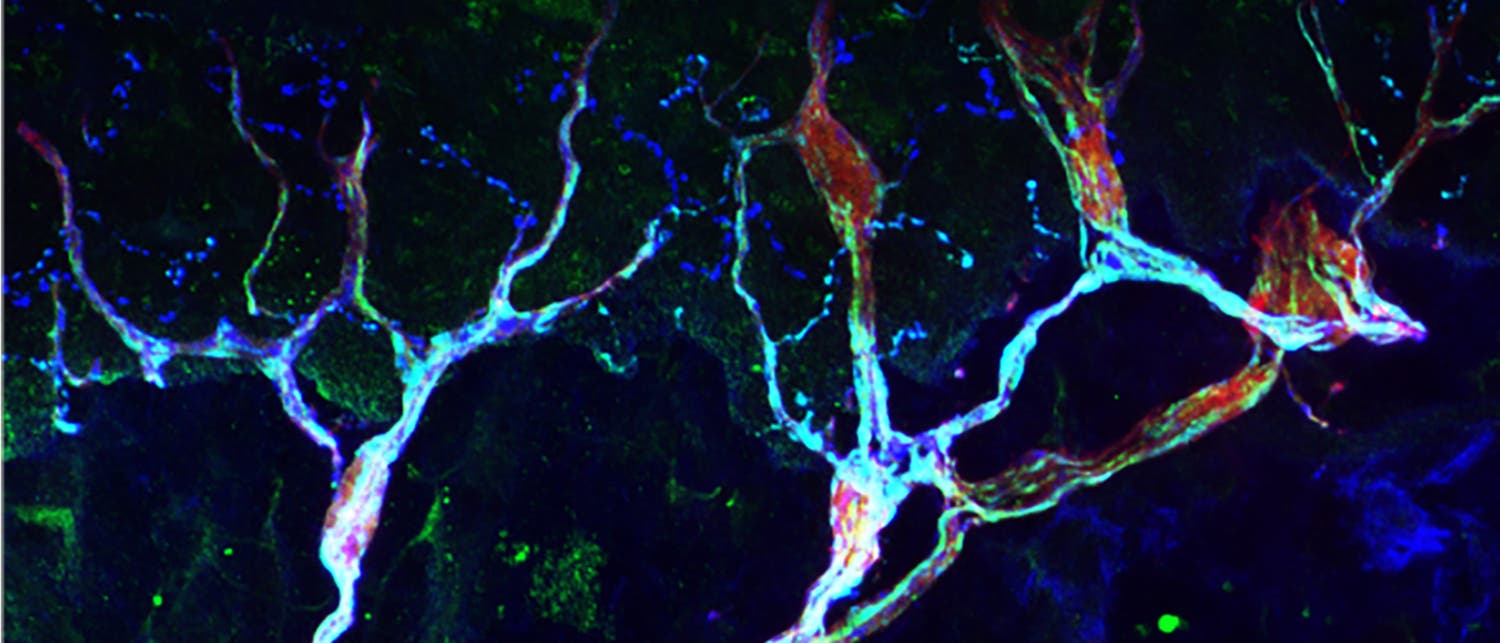

Bisher galten nozizeptive Nervenzellen als die einzigen Schmerzrezeptoren in der Haut. Ihre Nervenenden haben keine Myelinschicht und werden durch Druck, Hitze oder Kälte aktiviert. Laut den neuen Ergebnissen bilden sie aber zusammen mit den Schwannzellen einen Komplex in der Haut; beide Zelltypen sind wohl für die Schmerzwahrnehmung zuständig. Die nozizeptorischen Schwannzellen reagieren dabei nur auf Druck und nicht auf Temperaturunterschiede. Sie haben lange Ausläufer, die in die oberen Hautschichten ragen.